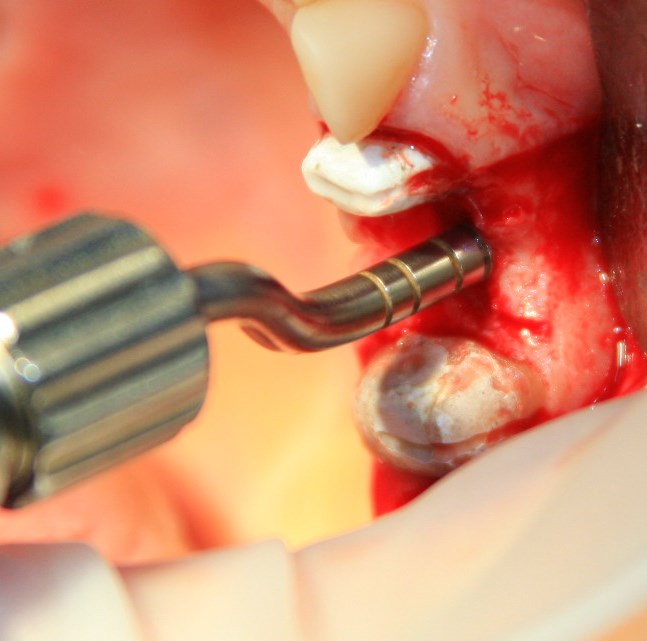

Здесь потребуется пародонтологический зонд с миллиметровой разметкой или какой-то другой измерительный прибор (операционная линейка). Ранее по КЛКТ я измерил костный дефект, теперь нужно нанести границы будущего костного блока на донорскую зону.

Ремарка: некоторые доктора предлагают делать хирургические шаблоны или выкройки специально для точного забора костного блока. На мой взгляд, это чрезмерное усложнение - во-первых, использование подобных шаблонов или выкроек требует увеличения площади раны, во-вторых, это увеличивает время и стоимость лечения, в-третьих, на этом этапе не требуется высокая точность, поскольку блок всё равно потребует адаптации.

Иными словами, важна не точность, а быстрый, аккуратный и, что главное, малотравматичный забор аутотрансплантата.

Для получения костного блока мы использовали ультразвуковую пьезохирургическую систему. Это самый удобный и безопасный инструмент для проведения подобных манипуляций. С помощью него мы сформировали и выделили костный блок. Он должен отделяться легким движением остеотома или элеватора. Как это сделать правильно — читай здесь>>